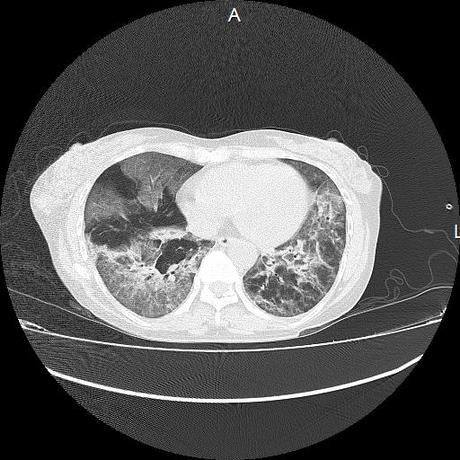

El parénquima pulmonar con areas parcheadas difusas en vidrio despulido combinadas con otras areas hipodensas de baja atenuación debidas a atrapamiento aéreo y engrosamiento intersticial y zonas de fibrosis de predominio en lóbulos medios e inferiores de ambos pulmones.

- LOS HALLAZGOS PUEDEN ESTAR EN RELACIÓN A NEUMOPATIA INTERSTICIAL PROBABLE ETIOLOGIA HIPERSENSITIVA VS AUTOINMUNE/BACTERIANA/FUNGICA.